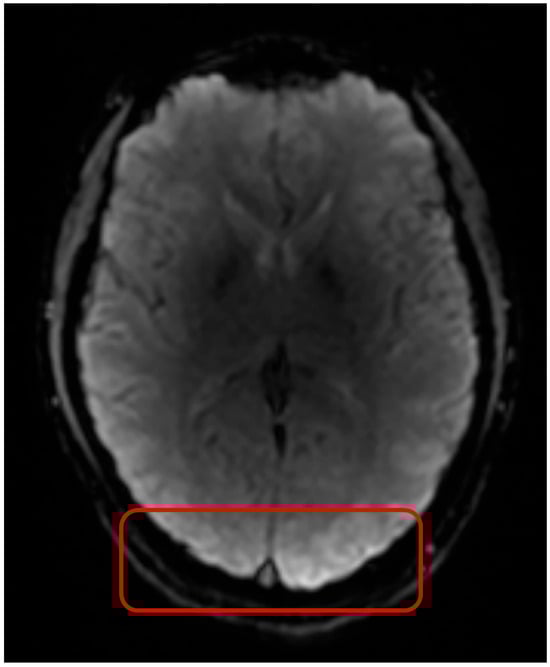

Figure 1. Normalized Dynamic Susceptibility Contrast (DSC) MRI signal of a 3 × 3 × 3 mm3 cube region located in healthy brain tissue (region indicated by the red box). Normalization was the division of observed signal intensity by max observed signal intensity.

Giving a basic overview of the DSC MRI method, DSC MRI uses an echo planar imaging (EPI) sequence to track a bolus of paramagnetic contrast agent over time [6,7]. The acquisition of DSC MRI starts prior to the injection of the contrast agent, to obtain baseline images unaffected by the contrast. Due to the paramagnetic properties of the contrast agent, a drop in T2*w and T2w signal intensity is observed when the contrast agent passes through the tissue (Figure 1). The paramagnetic properties of the contrast agent increase local magnetic field inhomogeneities. This leads to faster dephasing of transverse magnetization, resulting in a loss of signal intensity during contrast bolus passage. As the contrast agent consists of large hydrophilic molecules (547 Da), they cannot pass through the blood–brain barrier (BBB) and hence the contrast agent resides in blood [8,9]. Therefore, the change in signal intensity after injection of contrast agent as detected with DSC MRI, can be used to obtain indices like mean transit time (MTT), cerebral blood volume (CBV), and cerebral blood flow (CBF), and time between the peak of arterial input and residue function (Tmax), which reflect the hemodynamic properties of the tissue through which the contrast travels [6,7,10,11]. However, this assumption that contrast agents are not able to cross the BBB does not hold for all conditions. For instance, brain tumors often have a leaky BBB, resulting in contrast agent leakage into the extracellular space [12,13]. To maintain the accuracy of parameter estimations, a leakage correction can be performed. Furthermore, parameter estimations can be affected by image artefacts, which could impact the diagnostic value of the images.